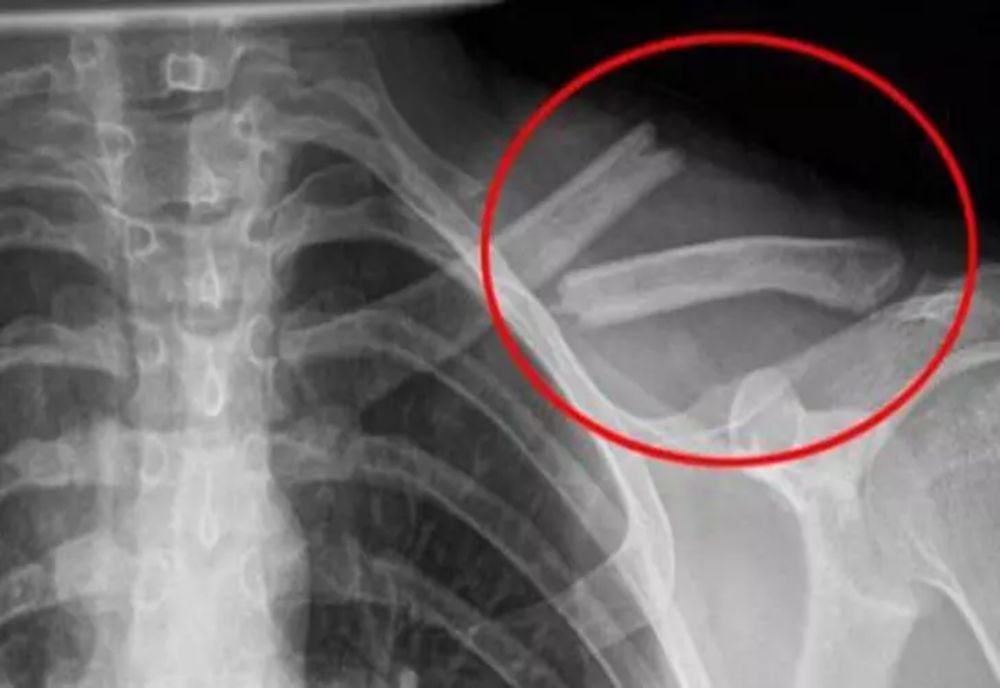

24 ian. 2023, 08:55ActualitateOtrava asta îţi distruge oasele! O bei în fiecare zi fără să știi cât de toxică este pentru organism